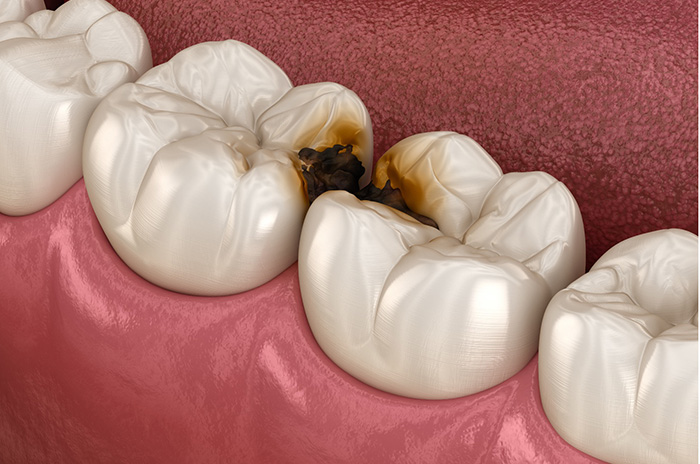

10 歯と歯の間が虫歯になった

できた虫歯の箇所が問題になります。噛む面や歯の表面の虫歯は、歯ぎしり・食いしばりとは全く別物になります。歯ぎしり・食いしばりが原因でできる虫歯は、歯と歯の間の虫歯になります。

なぜかというと歯ぎしり・食いしばりをすると歯と歯の間が擦れます。擦れた部分は、唾液が少ないので再石灰化しにくいです。再石灰化しない状態が、続くと歯ぎしり・食いしばりでまた、歯と歯の間が擦れてしまいます。そうなると負のループが止まらなくなり、虫歯が進行してしまいます。

また、歯と歯の間の虫歯は見えにくいので、知らない間に進んでいるという傾向が強いです。歯と歯の間の虫歯がエナメル質から象牙質に進行すると一気に進みますので注意が必要です。